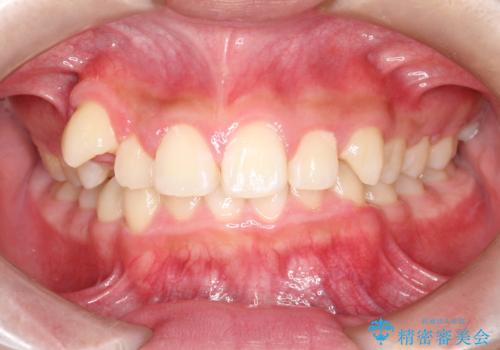

八重歯・歯並びのデコボコとディープバイトを改善した抜歯ワイヤー矯正症例

- 八重歯と咬み合わせを治したいを主訴にご来院された患者様です。

矯正の精密検査の結果上顎左右4番の計2本を抜歯し、審美性に配慮したワイヤー矯正装置(審美装置)を用いて治療を行いました。

八重歯などの歯列のデコボコが綺麗に改善され、患者様にも大変喜んでいただけました。また、咬み合わせが深い「ディープバイト」も併せて改善し、見た目だけでなく機能面でもバランスの取れた咬合を獲得しています。